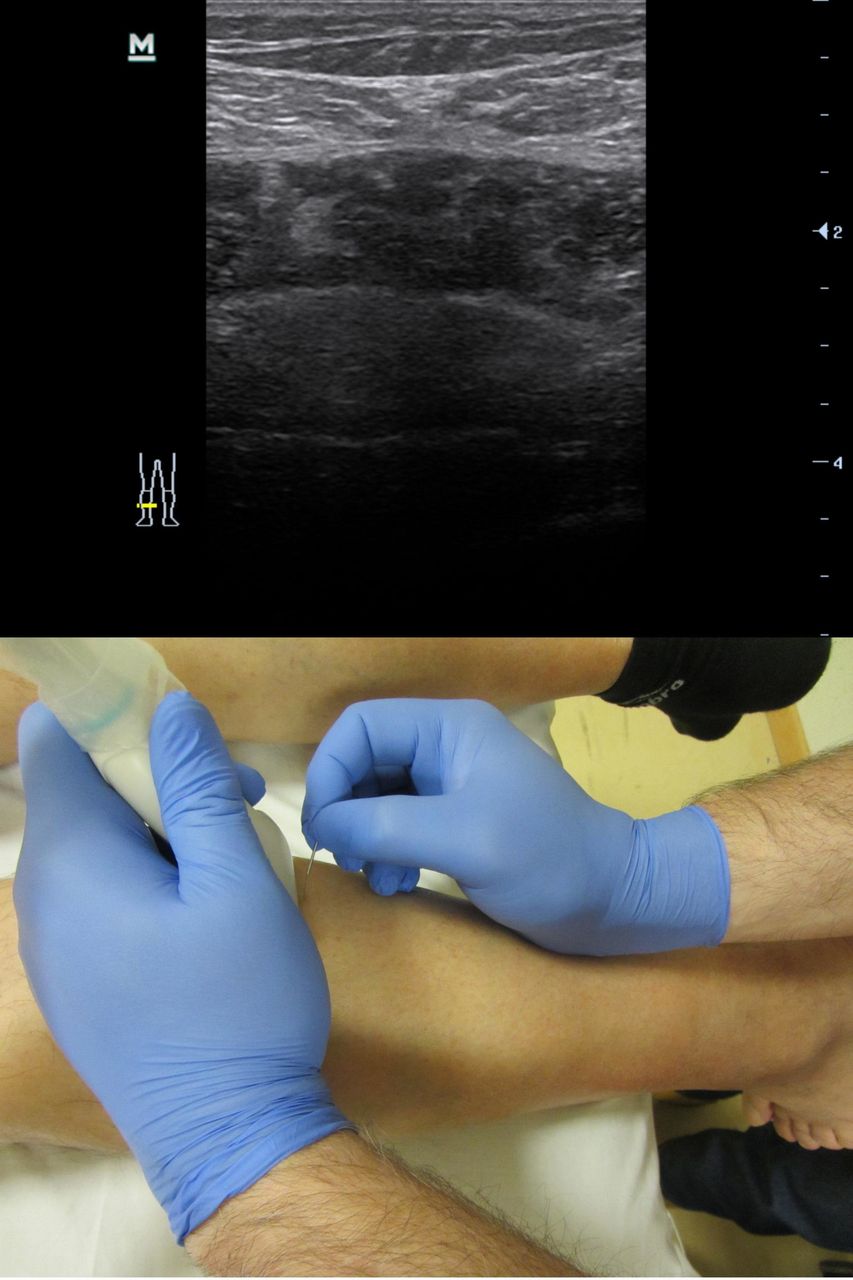

Needling runners’ knees

Inspired by Siqueira et al 2018.[1] A shot from the Ealing half marathon 2018 at around the 9 mile point - my arms were aching after taking over 2k of photos through a heavy zoom lens whilst waiting for my boy (5448) to come past 😀 This paper popped up on PubCrawler this morning. I’m … Continue reading Needling runners’ knees